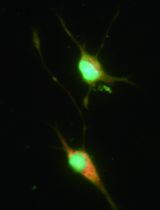

Isolation and Characterisation of Dendritic Cells from Peripheral Blood

外周血液中树突细胞的分离和特性描述